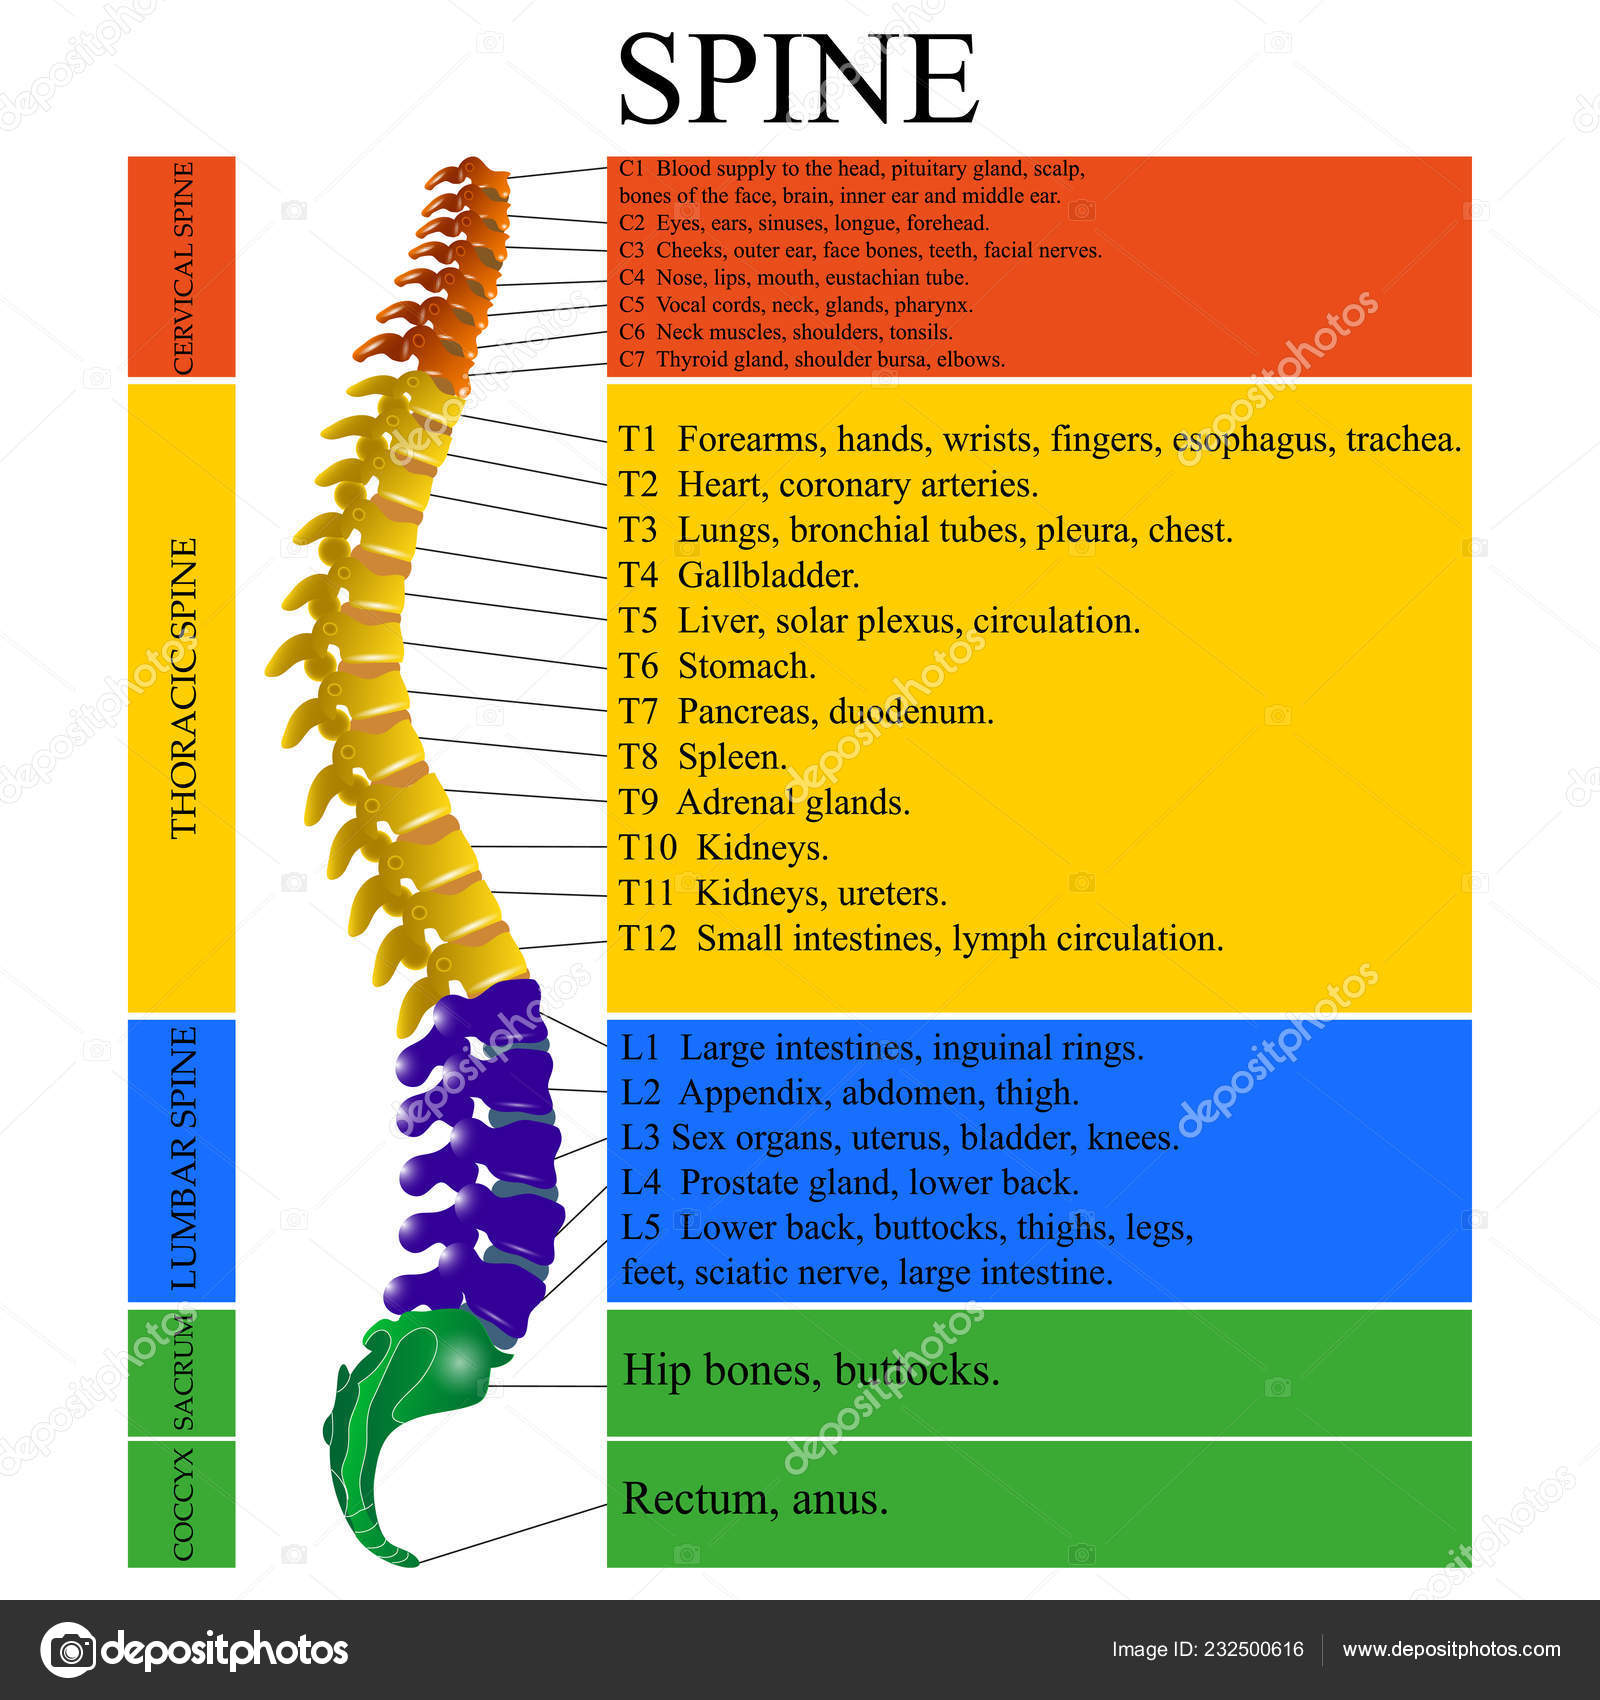

silikonsheet.blogg.se – Spine diagram

YOUR SPINAL COLUMN – Back To Life Chiropractic

spine+diagram | SPINAL NERVES & EFFECTS CHART | Nursing | Anatomia y …